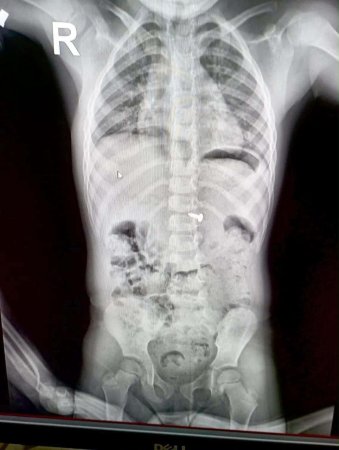

Діти пізнають світ на смак, і часто це призводить до небезпечних ситуацій. Проковтування дрібних речей — одна з найчастіших причин звернення до дитячих хірургів. Розповідаємо, які предмети несуть смертельну загрозу та як діяти батькам.

Деякі речі діють всередині організму як «тихі вбивці». Якщо дитина проковтнула щось із цього списку — негайно до лікарні:

Гострі предмети: Голки, шпильки чи уламки іграшок можуть травмувати внутрішні органи.